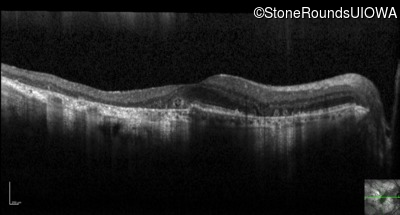

Optical Coherence Tomography - Left - 20/40 +1

Exemplar / OCT Stack

OCT Stack